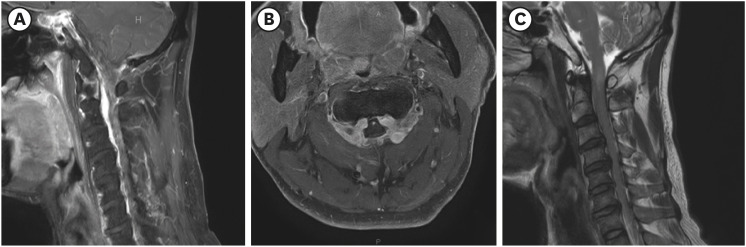

We present a case of cervical myelopathy caused by epidural hematoma formation due to chronic cerebrospinal fluid overdrainage. A 55-year-old man who underwent ventriculoperitoneal (V-P) shunt surgery for normal pressure hydrocephalus presented with progressive weakness of both the upper and lower extremities. Magnetic resonance imaging (MRI) revealed compressive myelopathy at the cervicomedullary junction at the C1-C2 level caused by epidural hematoma formation due to intracranial hypotension (IH) caused by a complication of V-P shunt. He underwent decompressive laminectomy and hematoma removal at C1-C2 and replacement of the V-P shunt valve. Follow-up cervical spine MRI showed an improved state of severe central spinal stenosis at the C1-C2 level and an improved state of compression-related cord signal intensity change in the spinal cord. After surgical intervention and intensive rehabilitation, the patient showed clinical improvement. If cervical myelopathy is suspected in patients with a shunt, cord compression due to venous engorgement or hematoma caused by over-shunting and IH should be considered.

Abstract Image